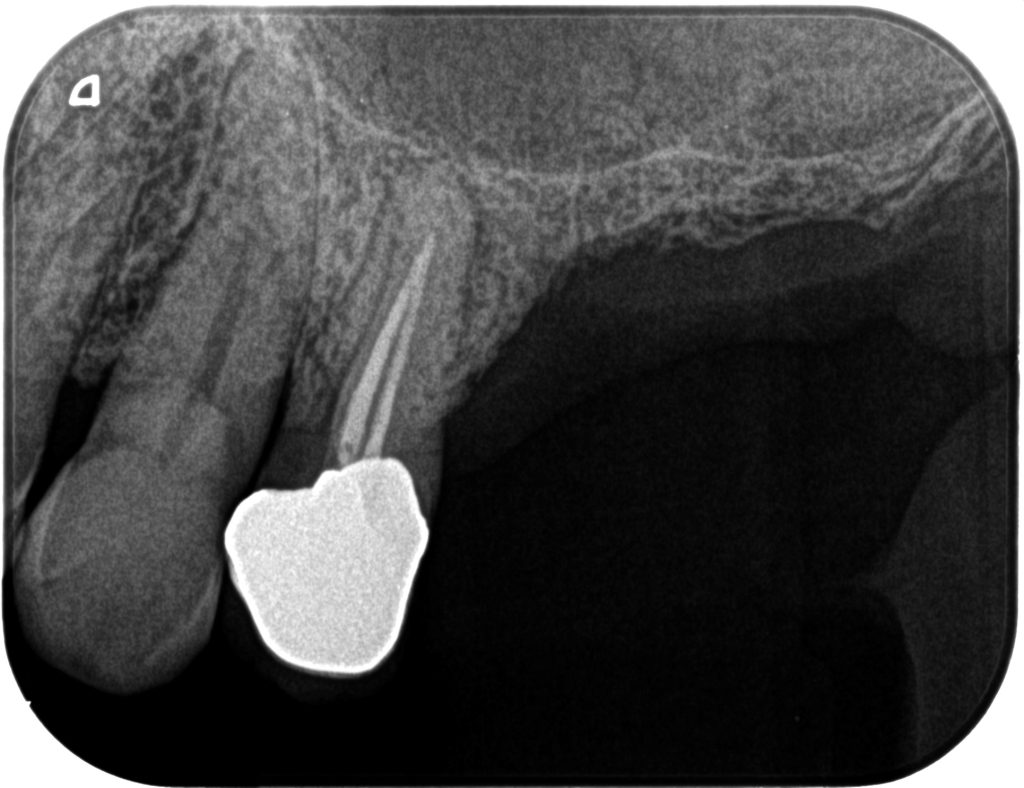

症例130代 女性 歯根破折にて右上6番を抜歯

治療前

ブリッジ・義歯・インプラントの選択肢を提案。

両隣在歯を削り、より負担のかかるブリッジや義歯は選択肢にはなく、両隣在歯を守るインプラントを選択。

骨高不足の為、ソケットリフト(上顎洞洞底膜挙上術)を適用。

オペ後、骨との密着値も良く、約2ヶ月後にはジルコニアを装着し終了。

リスクとしては外科的侵襲がある。デメリットは、保険外診療の為、経済的負担がある。

費用 64万(税込)(オペ・仮歯・最終補綴物まで含む)